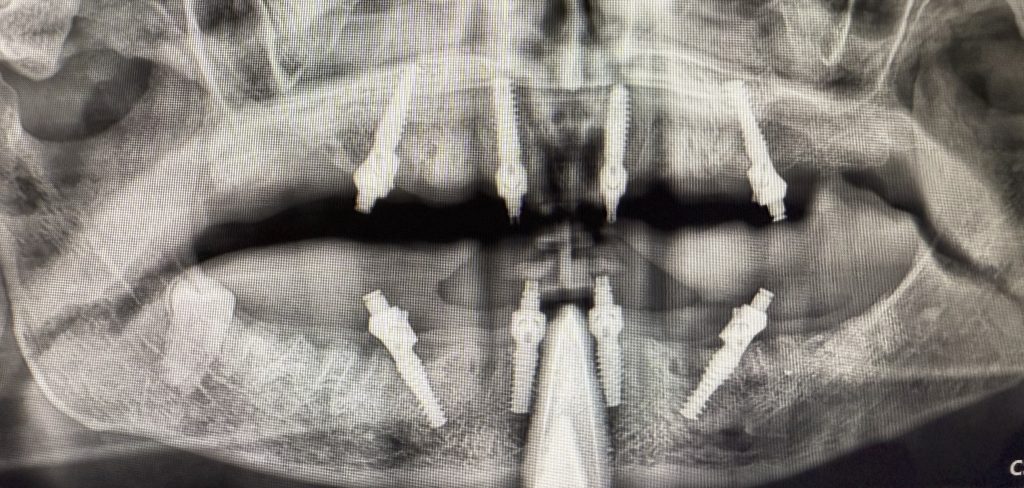

Previa anestesia locale con articaina 1:100.000, è stata fissata la dima guidata con frese di preparazione per i tre pin di fissaggio. Quindi, seguendo in sequenza le frese così come indicato per ogni sito implantare, sono stati inseriti i sei impianti mono-componente con MUA integrato B&B Dental con un torque d’inserzione di 35 N/cm. È stata eseguita una ops di controllo (Figure 8-13).

I file STL sono stati poi sovrapposti ai file DICOM della TC Cone Beam con un software dedicato di progettazione guidata B&B Dental. Tramite questo software di chirurgia guidata è stata stabilita la posizione degli otto impianti, da posizionare con l’ausilio di una dima chirurgiche a supporto mucoso fissata con tre pin ossei (Figure 3-4).